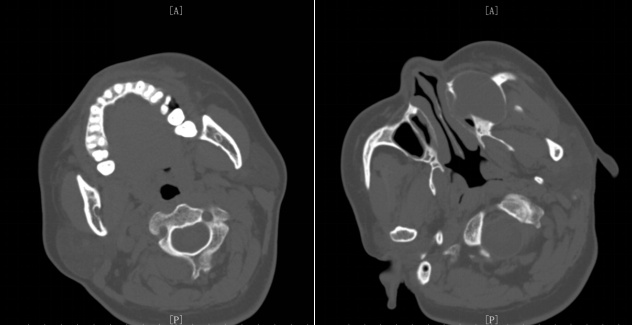

术前影像学检查:MRI检查及CT检查示左侧上颌骨内囊肿样病变,直径约4.0厘米,周围骨质呈压迫性吸收,左侧上颌窦腔被压迫缩小。